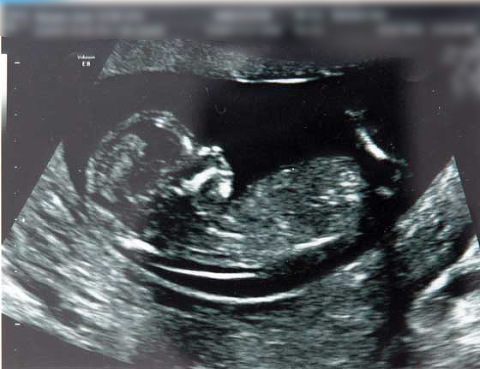

13 week scan. Boy or Girl?